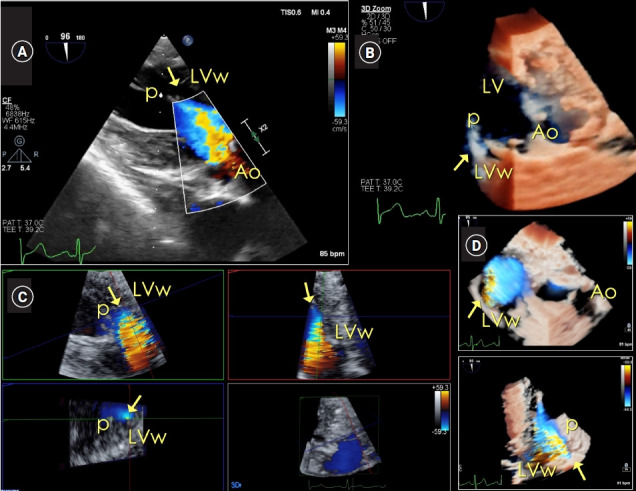

Case: In a 63-year-old female patient undergoing elective thoracic surgery, the systolic murmur was auscultated on the right sternal border of the second intercostal space in the preoperative patient holding area. Point-of-care (POC) transthoracic echocardiography (TTE) demonstrated a systolic jet flow in the LVOT area. The peak systolic velocity of the continuous wave Doppler tracing, aligned to the LVOT and the AV, was approximately 1.5 m/s. The peak/mean pressure gradient was 11/6 mmHg for the AV and 9/5 mmHg for the LVOT. Anesthesia was induced under continuous TTE imaging. Intraoperative transesophageal echocardiography also confirmed the absence of any cardiac pathology.

背景:病例:一名 63 岁的女性患者在接受胸外科择期手术时,在术前病人留置区第二肋间的胸骨右缘听诊到收缩期杂音。床旁(POC)经胸超声心动图(TTE)显示左心室出口区域有收缩期射流。对准左心室出口和房室的连续波多普勒描记的收缩期峰值速度约为 1.5 米/秒。房室的峰值/平均压力梯度为 11/6 mmHg,左心室出口的峰值/平均压力梯度为 9/5 mmHg。在连续 TTE 成像下进行麻醉。术中经食道超声心动图也证实没有任何心脏病变:POC超声心动图为意外发现的收缩期杂音提供了全面的术前评估,避免了传统术前超声心动图评估可能导致的手术时间延迟。